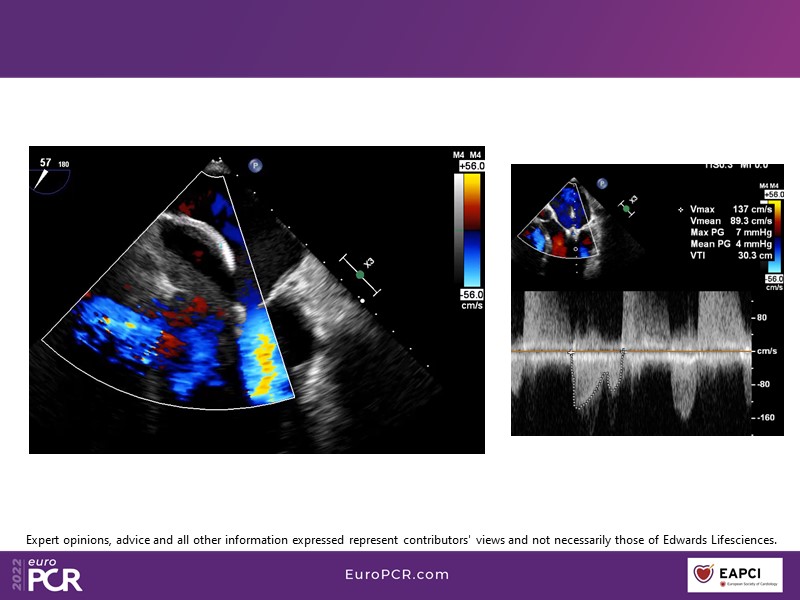

With study outcomes and clinical cases, this EuroPCR 2022 session will enable you to discuss the anatomical considerations that define suitable candidates for treatment of mitral regurgitation with the PASCAL platform and highlight key differentiators and tips and tricks for its use.

- To discuss which anatomical considerations define suitable candidates for the treatment of mitral regurgitation with the PASCAL platform

- To attend case-based discussions that will highlight key differentiators and tips and tricks when using the PASCAL platform to treat mitral regurgitation